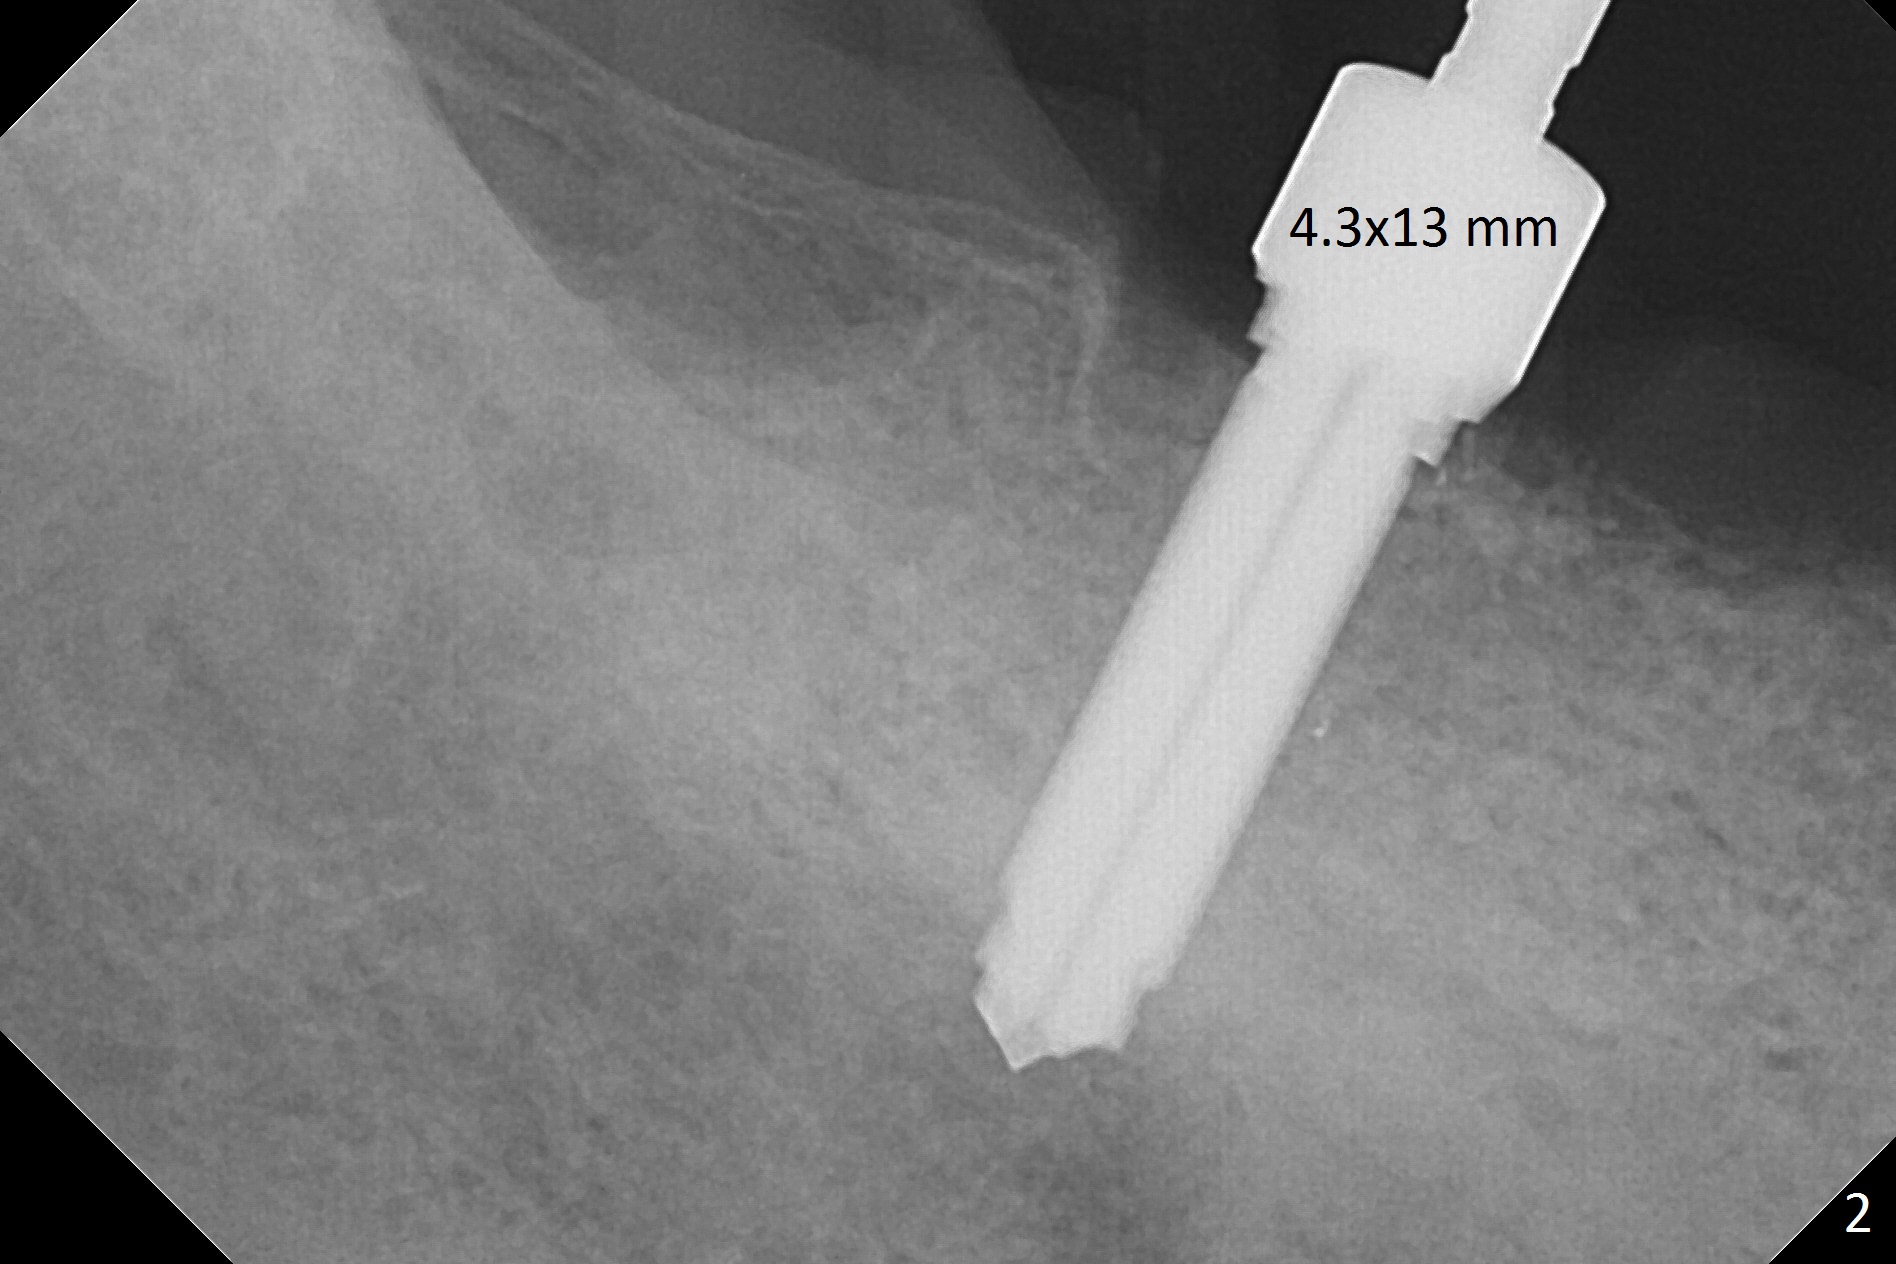

There are 2 challenges associated with #31 implant placement: indistinct Inferior Alveolar Canal (Fig.1-4) and difficulty in fabrication of a provisional (Fig.5).  After placing a 5.5x13 mm implant (Fig.3 supracrestal (<)), it is removed for apical resection for ~ 2 mm; when it is reseated, it is subcrestal (Fig.5 <).  A simplified temporary provisional (Fig.5 P) is fabricated around a 6.5x4(4) mm abutment (A) without adapting the lower RPD.  The patient is advised not to wear the latter.  When the socket heals, there will be 2 options: no provisional or a new one.  The latter should have good retention to the abutment and no contact with the lower RPD in and out.